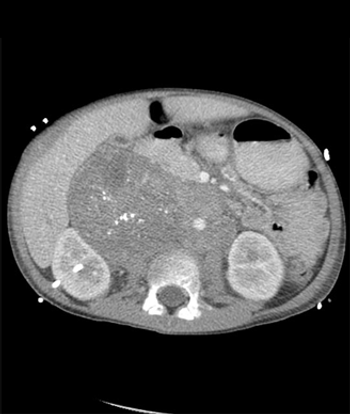

A recent study highlights factors that predict worse prognosis for patients with germ cell tumors whose cancer has spread to the brain, including the presence of liver or bone metastases, multiple brain metastases, and others.